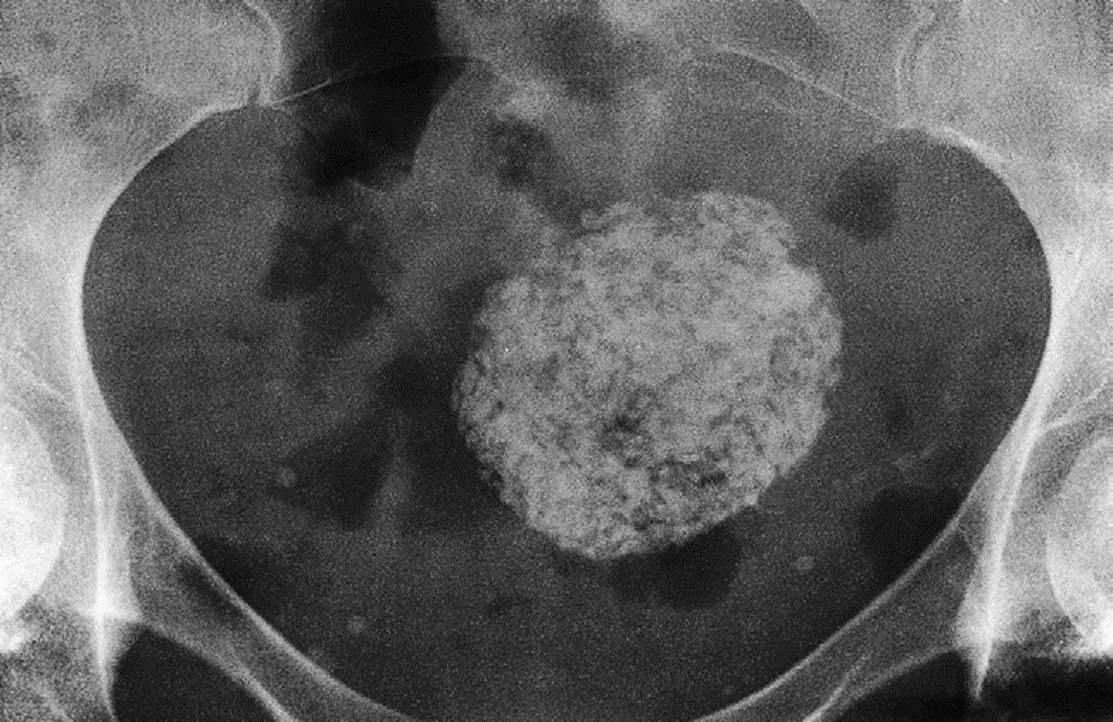

Calcified Uterine Leiomyoma Plain radiograph :

When sufficiently large, a fibroid can be seen on a plain film as a mass in the pelvis and may show multiple irregular but well-defined calcifications

Calcification in a large uterine fibroid.